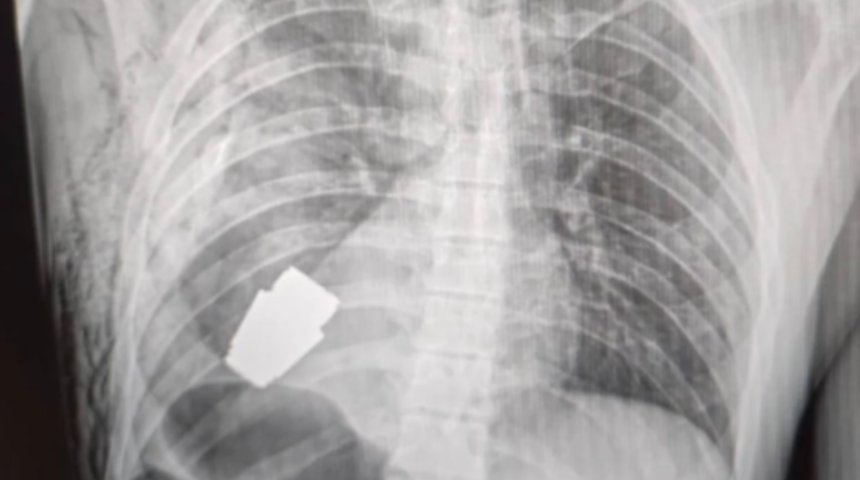

Ukrayna ordusunda görev yapan ismi açıklanmayan bir askerin kalbine yakın bölgesinde VOG el bombası tespit edildi. Bombanın her an patlayabilme ihtimali olduğu için Ukrayna Silahlı Kuvvetlerinin en deneyimli cerrahlarından biri olan Andrii Verba tarafından acil bir operasyon gerçekleştirildi.

Ukrayna Savunma Bakanı Yardımcısı Hanna Maliar, cerrahi müdahalenin başarılı olduğunu ve askerin tedavi altına alındığını söyledi. El bombasının askerin vücuduna nasıl girdiğine dair ise açıklama yapılmadı. (İHA)